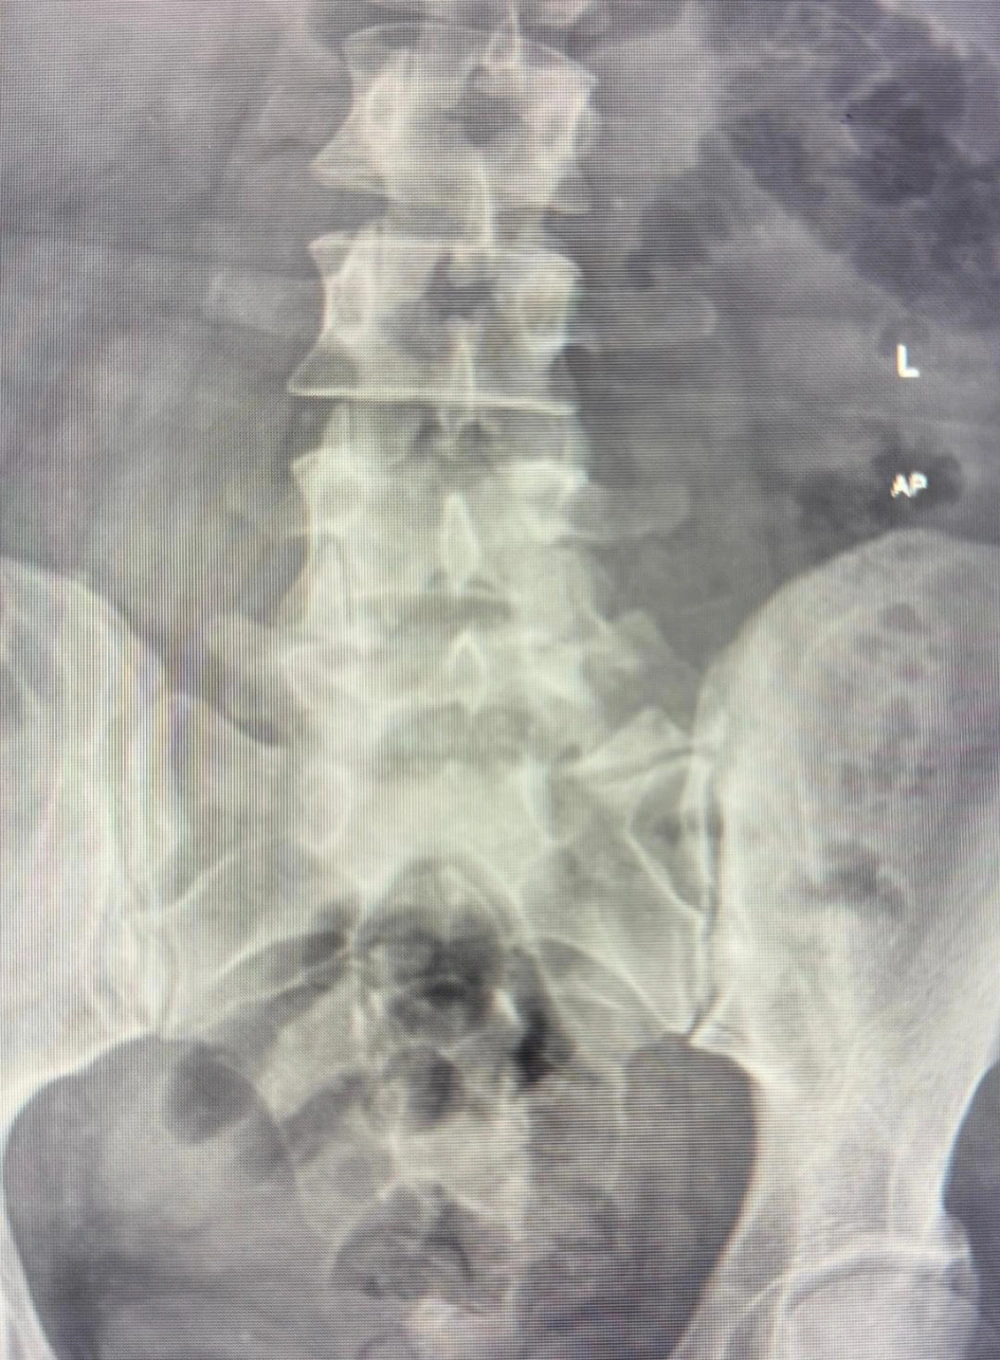

A review of the pre-procedure lumbosacral (L-S) X-rays identified a bifid right L5 transverse process and an enlarged left transverse process (Figure 1). Based on these findings, a right-sided posterolateral approach was selected, with the goal of achieving bilateral spread of contrast. A left-sided trans-discal approach was planned as a contingency in case the attempt resulted in unilateral contrast distribution (7, 8).

Anteroposterior (AP) view of the lumbosacral (L-S) spine. This image reveals a bifid transverse process on the right side at the L5 vertebral level. In contrast, the left transverse process of L5 appears distinctly enlarged compared to the right side and the transverse processes of the adjacent vertebrae.